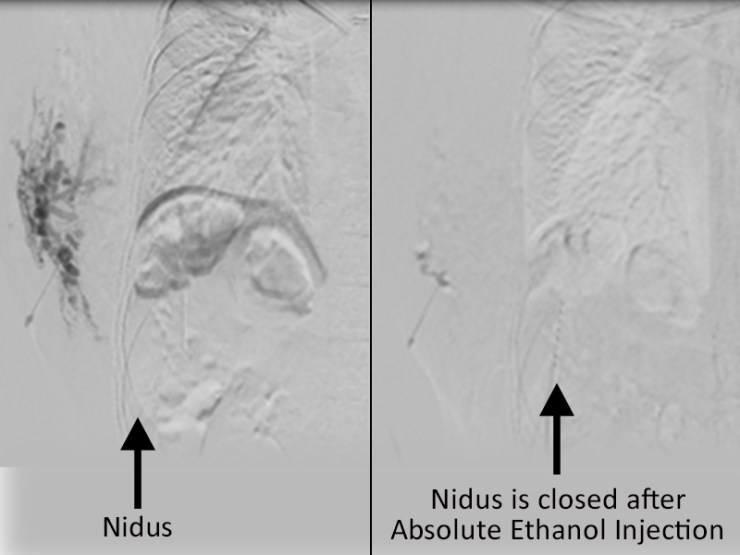

Absolute ethanol embolization is the only effective solution to destroy nidus.

Absolute ethanol if injected into nidus directly it will destroy inner lining cells of the nidus and nidus will resolve by it.

Case 1: Venous malformation of chest wall, suffering from many years. With our treatment pt’s pain disappeared within 3rd sitting.